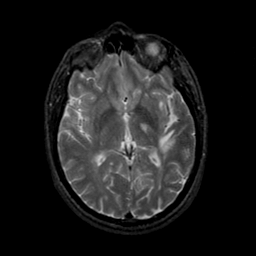

MR Study #23, January 26, 1992 -- Slice #25